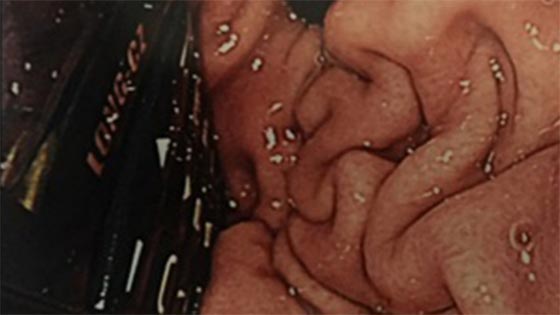

بعد أن ابتلع هاتفا في بطنه، ظل سجين إيرلندي يتقيأ أربع ساعات قبل أن ينقل إلى المستشفى. وواجه المسعفون حالة نادرة عندما وجدوا السجين البالغ من العمر 29 عاما في حالة يرثى لها. وأظهر فحص الأشعة السينية أن الهاتف موجود في داخل بطن السجين. وحاول المسعفون في بداية الأمر إخراج الهاتف عبر إدخال منظار طبي إلى جوف السجين، لكن هذه المحاولة أخفقت.

وأشاروا إلى أن الأمر يتطلب إجراء عملية شق البطن وإخراج الهاتف الذي استقر في المعدة، واستطاعوا في نهاية المطاف إخراج الهاتف من خلالها. وأظهرت الأشعة السينية ان الهاتف المحمول الذي ابتلعه السجين والبالغ من العمر 29 عاما سليم ولم يتأثر بالحامض المعدي. وقال أطباء لمجلة طبية إن هذه الحالة تشير إلى أن الحاجة ماسة إلى سرعة إجراء عمليات جراحية في حالات مماثلة. وأوضحوا أن ابتلاع الأجسام الصغيرة يمكن التخلص منها عبر المنظار، لكن في حالة الهاتف المحمول فإن الأمر يحتاج عملية جراحية.